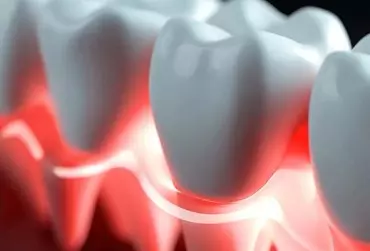

Zapalenie przyzębia jest powszechną chorobą jamy ustnej, która dotyka ponad połowę populacji świata. Zapalenie przyzębia jest związane z ogólnoustrojowym stanem zapalnym, biorącym udział w patogenezie wielu chorób układu krążenia (m.in. nadciśnienia tętniczego, postępu miażdżycy). Migotanie przedsionków, najczęstsze zaburzenie rytmu serca, występuje częściej u pacjentów z zapaleniem przyzębia (zwłaszcza jego cięższych postaci). Ponadto zapalenie przyzębia występujące u mniej więcej jednej piątej pacjentów z migotaniem przedsionków przyczynia się do gorszego rokowania (nawrót arytmii, zwiększone ryzyko udaru). Utrzymywanie higieny jamy ustnej i leczenie przyzębia to udokumentowany sposób zapobiegania nowym przypadkom migotania przedsionków i poprawy rokowania pacjentów z iistniejącym migotaniem przedsionów. W niniejszym artykule podsumowano kluczowe aspekty dotyczące zapalenia przyzębia i migotania przedsionków.

Zapalenie przyzębia jest bardzo powszechną chorobą jamy ustnej. Objawy tego schorzenia nie są jednak bardzo dotkliwe na wczesnych etapach rozwoju choroby. Powoduje to, iż nasi pacjenci ignorują symptomy, takie jak krwawienie w czasie szczotkowania czy rozwój recesji, i zgłaszają się do stomatologa dopiero, gdy są zaniepokojeni rozchwianiem zębów. Późne leczenie zapalenia przyzębia może mieć bardzo dotkliwe skutki dla zdrowia ogólnego. W ostatnich latach jest prowadzonych wiele badań na temat wpływu zapalenia przyzębia na zdrowie ogólne. Pokazały one, iż przewlekłe zapalenia, toczące się latami w naszych tkankach, są źródłem aktywacji komórek układu immunologicznego, które następnie mogą brać udział w etiopatogenezie wielu schorzeń ogólnych, w tym nadciśnienia tętniczego. Identyfikacja zapalenia przyzębia jako czynnika ryzyka nadciśnienia jest bardzo ważnym faktem, który stawia przed nami, stomatologami, kolejne wyzwanie jako przed lekarzami mogącymi czynnie uczestniczyć w prewencji choroby nadciśnieniowej u swoich pacjentów przez zapobieganie chorobom przyzębia i ich wczesne leczenie.